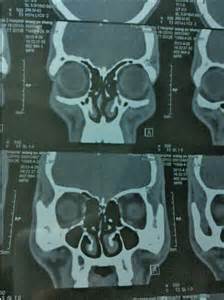

鼻中隔偏曲ct圖